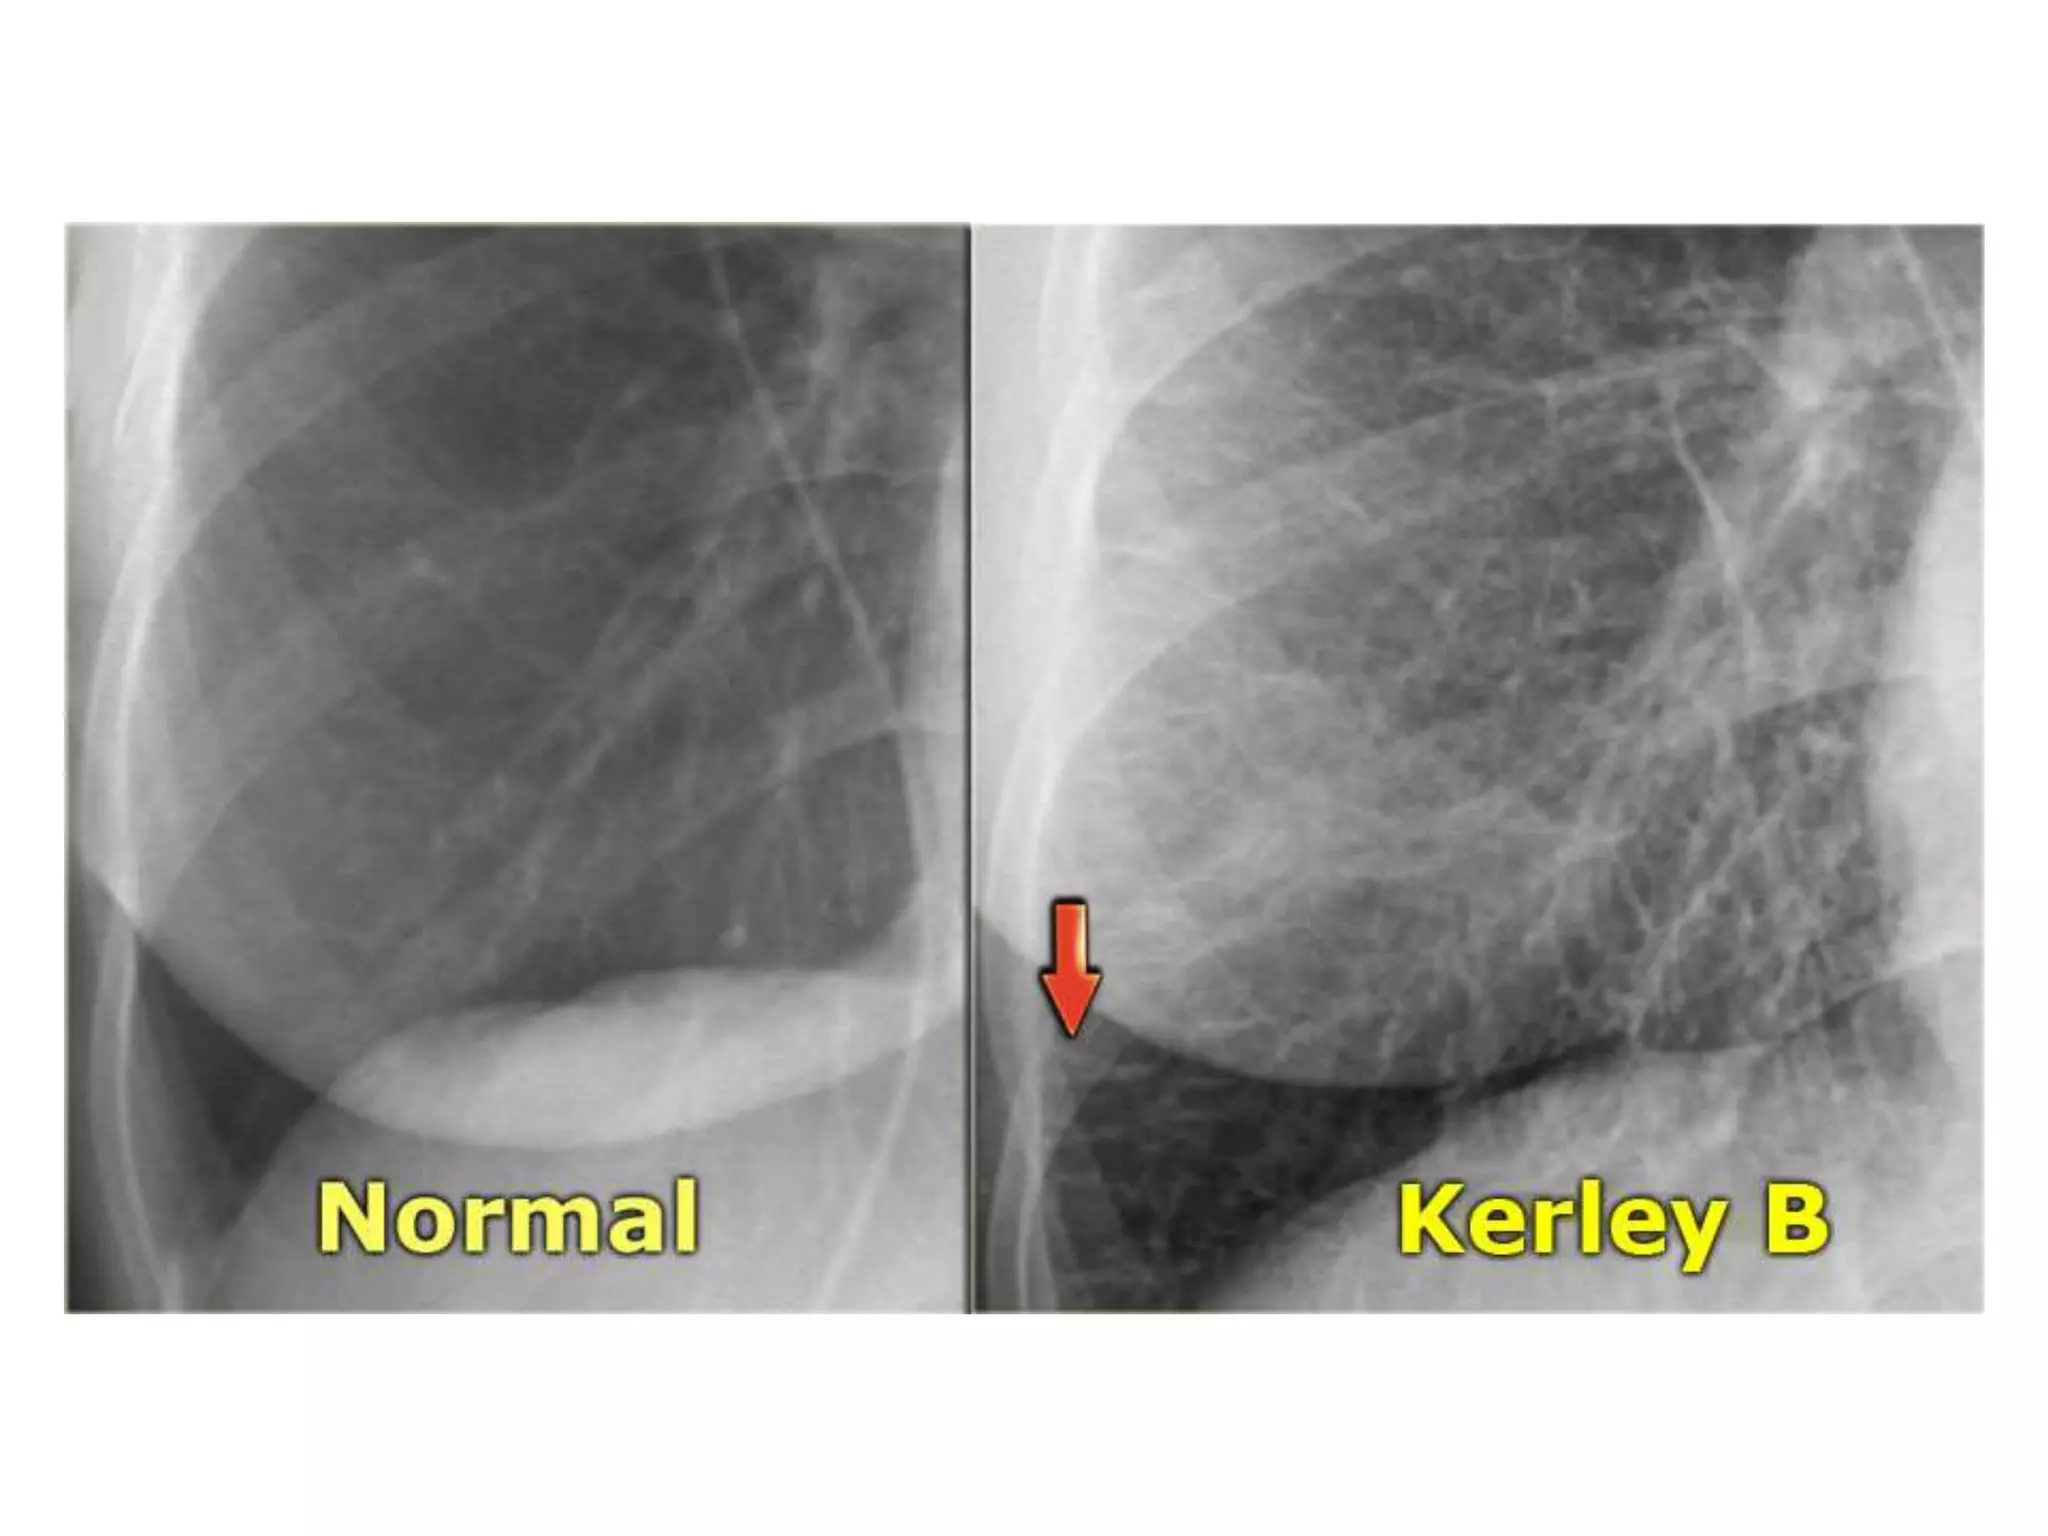

Congestive Heart Failure - Cardiovascular - Medbullets Step 1

failure heart medbullets congestive cardiovascular